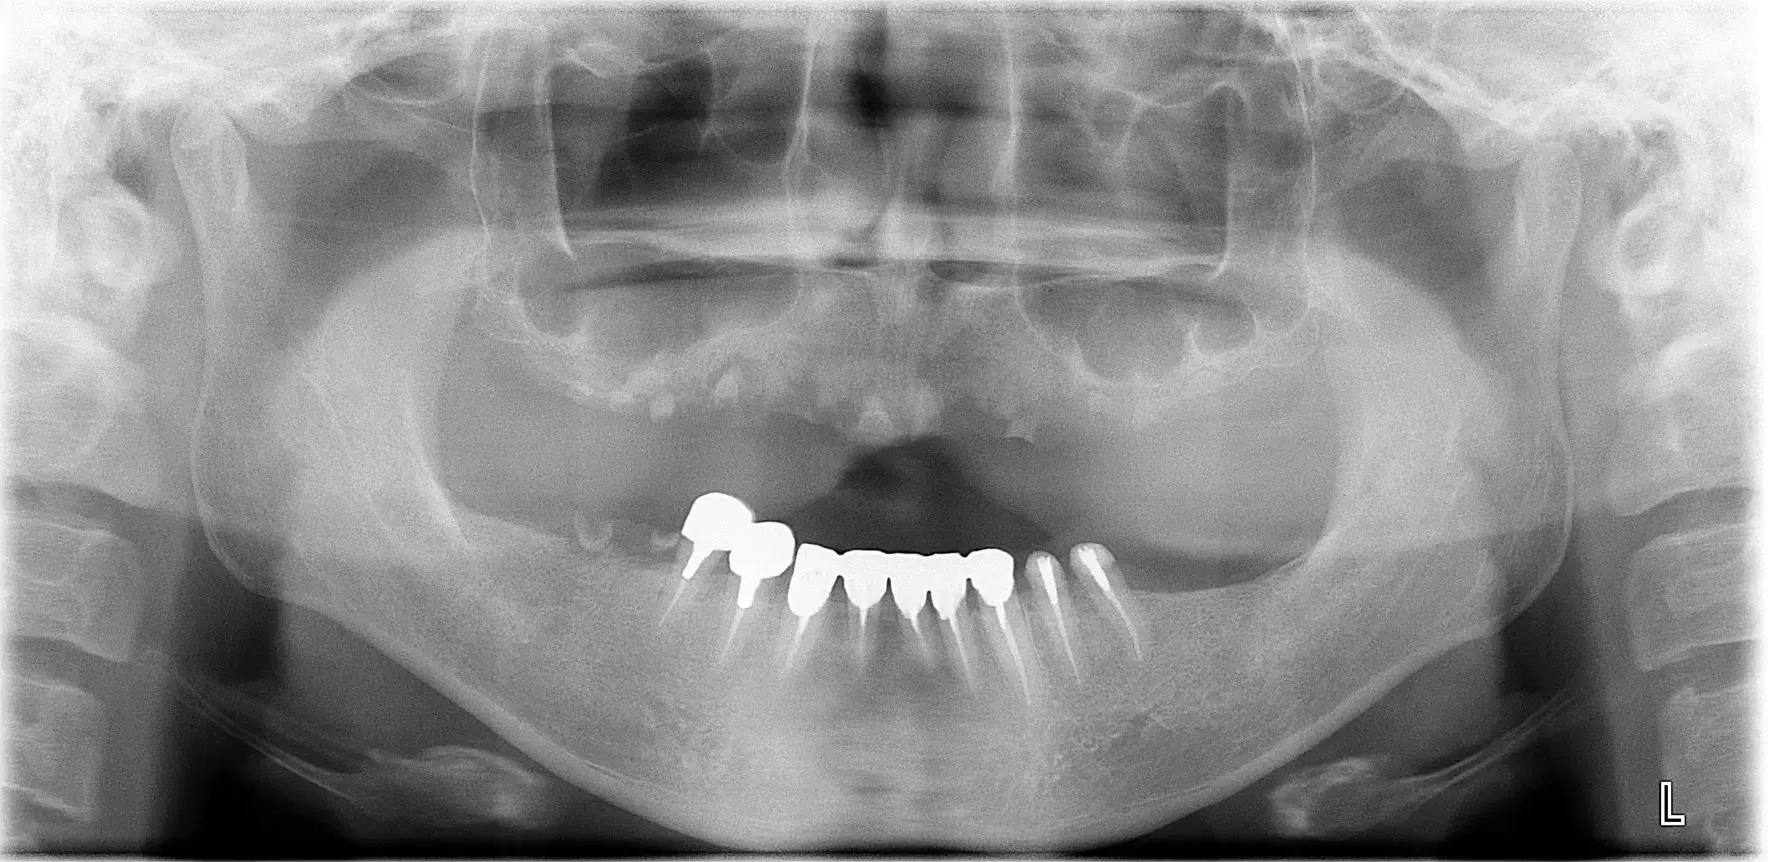

| 治療ケース | 下顎:オールオン4 歯科麻酔科医管理下にて静脈内鎮静・局所麻酔を行い、4本のインプラントを埋入し即時負荷。当日中に12本のプロビジョナル(仮歯)を装着。7ケ月後に上部構造オールセラミック装着。 |

| 症状 | さし歯が取れて入れ歯が合わなくなってしまいました。 |

| 治療結果 | 遠方から、入れ歯が合わないという主訴でご来院。オールオン4で即時負荷を行う事により、当日中にプロビジョナル(仮歯)が装着でき、すぐに食事ができるようになり、大変満足されています。 |

| 治療開始月 | 2022年4月 |

| 治療期間 | 約7ヶ月 |

| メインテナンスの頻度 | 3ケ月毎 |

| 治療を行う上での注意点(リスク / 副作用) |

外科手術を行う上で、下記のような症状が出るケースがあります。 ・インプラント埋入手術後の出血、腫れ、痛みを伴う可能性。内出血が皮膚に出現する可能性。 ・骨の状態により、インプラント埋入手術時に即時負荷が出来ない可能性。 ・歯科医師による術後の指導を受け入れて頂けない場合、インプラント体ロストの可能性。 (治療は全て、各患者さま固有の症例に対応したものです。他の方への治療結果を保証するものではないことをご了承ください) |